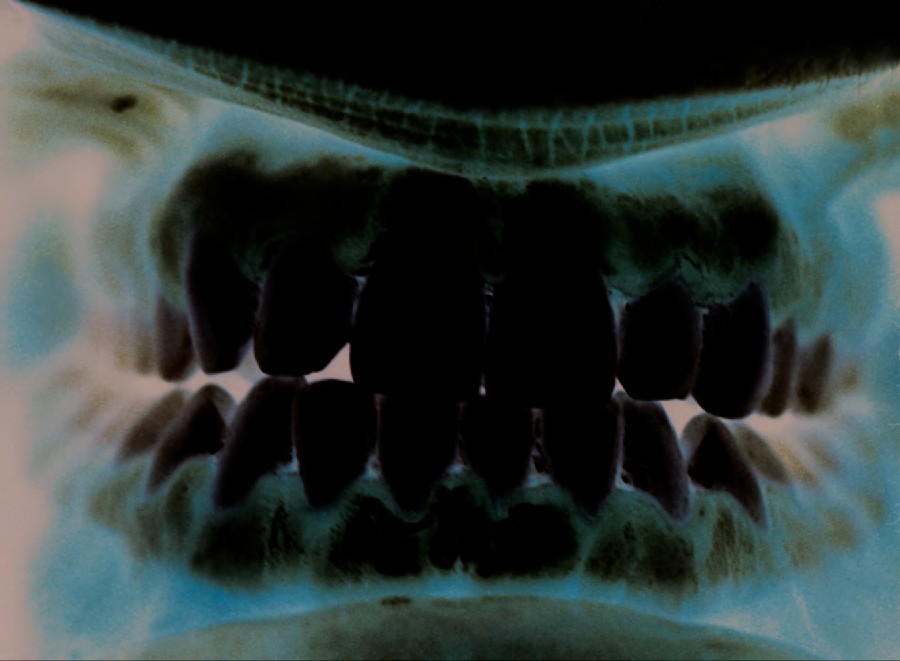

The structure of a tooth (Figure 24.4) begins with the visible outer surface, called the crown, which has to be extremely hard to withstand the force of biting and chewing. The crown is covered with enamel, which is the hardest material in the body. Underneath the crown, a layer of relatively hard dentin extends into the root of the tooth around the innermost pulp cavity, which includes the pulp chamber at the top of the tooth and pulp canal, or root canal, located in the root. The pulp that fills the pulp cavity is rich in blood vessels, lymphatic vessels, connective tissue, and nerves. The root of the tooth and some of the crown are covered with cementum, which works with the periodontal ligament to anchor the tooth in place in the jaw bone. The soft tissues surrounding the teeth and bones are called gums, or gingiva. The gingival space or gingival crevice is located between the gums and teeth.

Figure 24.4 The tooth has a visible crown with an outer layer of enamel, a layer of dentin, and an inner pulp. The root, hidden by the gums, contains the pulp canal (root canal). (credit: modification of work by Bruce Blaus)

Tooth decay results from the metabolic activity of microbes that live on the teeth. A layer of proteins and carbohydrates forms when clean teeth come into contact with saliva. Microbes are attracted to this food source and form a biofilm called plaque. The most important cariogenic species in these biofilms is Streptococcus mutans. When sucrose, a disaccharide sugar from food, is broken down by bacteria in the mouth, glucose and fructose are produced. The glucose is used to make dextran, which is part of the extracellular matrix of the biofilm. Fructose is fermented, producing organic acids such as lactic acid. These acids dissolve the minerals of the tooth, including enamel, even though it is the hardest material in the body. The acids work even more quickly on exposed dentin (Figure 24.7). Over time, the plaque biofilm can become thick and eventually calcify. When a heavy plaque deposit becomes hardened in this way, it is called tartar or dental calculus (Figure 24.8). These substantial plaque biofilms can include a variety of bacterial species, including Streptococcus and Actinomyces species.

Figure 24.7 Tooth decay occurs in stages. When bacterial biofilms (plaque) develop on teeth, the acids produced gradually dissolve the enamel, followed by the dentin. Eventually, if left untreated, the lesion may reach the pulp and cause an abscess. (credit: modification of work by “BruceBlaus”/Wikimedia Commons)

Figure 24.8 (a) Tartar (dental calculus) is visible at the bases of these teeth. The darker deposits higher on the crowns are staining. (b) This tooth shows only a small amount of visible decay. (c) An X-ray of the same tooth shows that there is a dark area representing more decay inside the tooth. (d) Removal of a portion of the crown reveals the area of damage. (e) All of the cavity must be removed before filling. (credit: modification of work by “DRosenbach”/Wikimedia Commons)

Some tooth decay is visible from the outside, but it is not always possible to see all decay or the extent of the decay. X-ray imaging is used to produce radiographs that can be studied to look for deeper decay and damage to the root or bone (Figure 24.8). If not detected, the decay can reach the pulp or even spread to the bloodstream. Painful abscesses can develop.